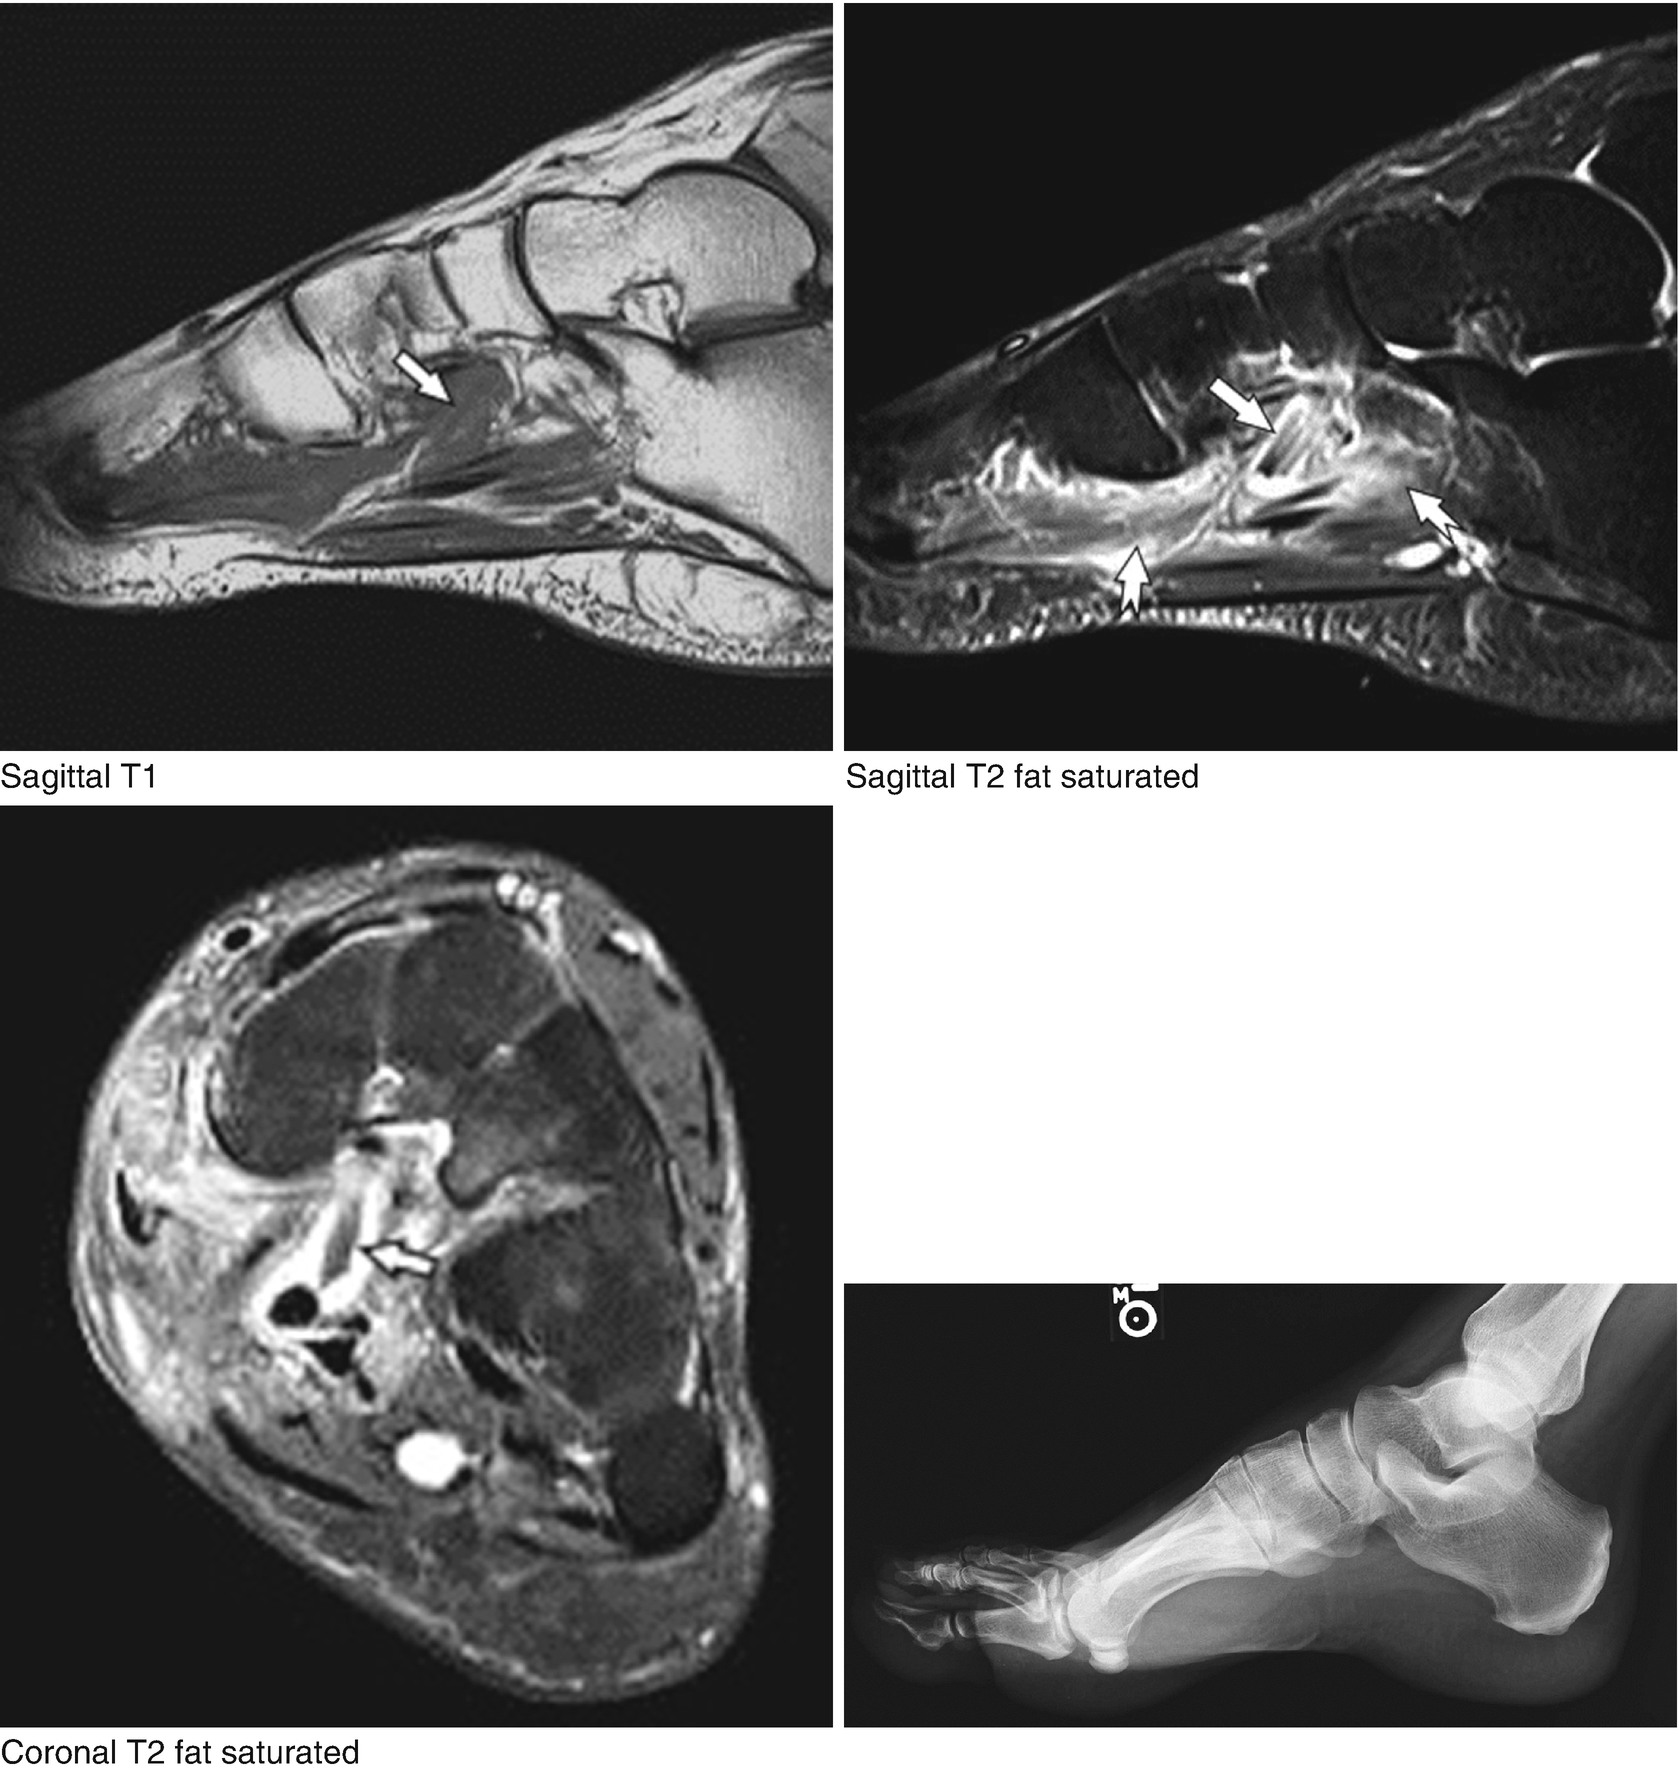

Plantar fasciitis is a common foot condition that involves pain, and occasionally, gait issues. It results in pain in the heel and bottom of the foot that is usually most severe with the first steps of the day or following a period of rest. Other diagnostic tests, such as magnetic resonance imaging (mri), may be done if doctors suspect the person's fascia is torn. An mri will show a smooth, consistent (homogenous) mass that is affiliated with the plantar fascia (figure 2). Stretching the calf muscles and foot often accelerates healing. To describe changes in activation of the intrinsic plantar foot muscles after 4 exercises as measured with t2 magnetic resonance imaging (mri). Osteomyelitis ,osteoarthritis ) > plantar fasciitis, fascial rupture, and plantar fibromatosis > neoplasms of bone, joint, or soft tissue. Indications for foot mri scan. A magnetic resonance imaging (mri) was performed on a normal subject; This weakness can cause slight. Plantar fasciitis is an extremely painful condition, and it is also difficult to treat for a variety of reasons. Learn vocabulary, terms and more with flashcards, games and other study tools. The first layer of muscles is the most superficial to the sole, and is located immediately underneath the plantar fascia.

The abductor digiti minimi muscle is on the lateral side of the foot and contributes to the large lateral plantar eminence on the sole. Plantar fasciitis is a disorder of the connective tissue which supports the arch of the foot. Top suggestions for plantar foot muscles mri. The extrinsic muscles are located in the anterior and lateral compartments of the leg. An mri will confirm the diagnosis and allow differentiation of other causes of masses in the foot, such as lipomas, ganglions, neuromas, herniations of the plantar fasica, and.

Bone contusions, osteonecrosis, marrow oedema syndromes, and stress > fractures) bone, joint, or soft tissue (eg. Top suggestions for plantar foot muscles mri. Most superficial of all the layers. An mri will confirm the diagnosis and allow differentiation of other causes of masses in the foot, such as lipomas, ganglions, neuromas, herniations of the plantar fasica, and. This weakness can cause slight. 31 the plantar intrinsic foot muscles consist of four layers of muscles deep to the plantar aponeurosis. • muscles of the plantar foot. Indications for foot mri scan.

Ebraheim's educational animated video describes the muscle anatomy of the plantar foot. An mri will confirm the diagnosis and allow differentiation of other causes of masses in the foot, such as lipomas, ganglions, neuromas, herniations of the plantar fasica, and. They are considered voluntary muscles. A mri scan is shown in figure 84. Indications for foot mri scan. To describe changes in activation of the intrinsic plantar foot muscles after 4 exercises as measured with t2 magnetic resonance imaging (mri). ► shoulder ► elbow ► wrist ► finger ► thumb. Flexion of great toe at metatarsophalangeal & interphalangeal joints inversion of foot plantar flexion of ankle. Start studying plantar foot muscles. Edited by brent brookbush dpt, pt, ms, pes, ces, cscs, acsm h/fs. Top suggestions for plantar foot muscles mri. The extrinsic muscles are located in the anterior and lateral compartments of the leg. Most superficial of all the layers.

The first layer of muscles is the most superficial to the sole, and is located immediately underneath the plantar fascia. The muscles acting on the foot can be divided into two distinct groups; The person may need to lose weight. ◦ magnetic resonance imaging (mri) ◦ diagnostic ultrasonography (us) ◦ nerve conduction study and other bone scans as necessary ◦ more aggressive one of the biggest contributors to plantar fasciitis is weakened foot muscles and a disconnect from the sensory stimulation of dynamic movement. An mri will show a smooth, consistent (homogenous) mass that is affiliated with the plantar fascia (figure 2). 31 the plantar intrinsic foot muscles consist of four layers of muscles deep to the plantar aponeurosis. Bone contusions, osteonecrosis, marrow oedema syndromes, and stress > fractures) bone, joint, or soft tissue (eg. Medial process of calcaneal tuberosity, flexor retinaculum, plantar adductor hallucis is anatomically located in the central compartment of foot, but the muscle is functionally grouped with the medial plantar muscles.

They are considered voluntary muscles. Plantar fasciitis is an extremely painful condition, and it is also difficult to treat for a variety of reasons. Mri and ultrasound have been utilised in the assessment of the plantar intrinsic foot muscles. Use of mri for volume estimation of tibialis posterior and plantar intrinsic foot muscles in healthy and chronic plantar fasciitis limbs. Other diagnostic tests, such as magnetic resonance imaging (mri), may be done if doctors suspect the person's fascia is torn. Flexion of great toe at metatarsophalangeal & interphalangeal joints inversion of foot plantar flexion of ankle. They are generally divided into two sets: Plantar flexion of the foot is the opposite movement of the dorsiflexion otherwise known as pointing your toes down. Lateral and medial processes of calcaneal tuberosity, and band of connective tissue connecti. Plantar fasciitis is a disorder of the connective tissue which supports the arch of the foot. Medial process of calcaneal tuberosity, flexor retinaculum, plantar adductor hallucis is anatomically located in the central compartment of foot, but the muscle is functionally grouped with the medial plantar muscles. Key facts about the medial plantar muscles. 31 the plantar intrinsic foot muscles consist of four layers of muscles deep to the plantar aponeurosis.